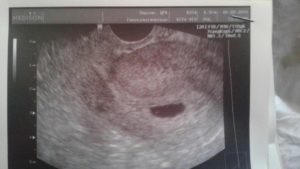

Это внутреннее УЗИ – оно проводится с помощью датчика, который вводят прямиком во влагалище. Такая процедура рекомендуется на ранних сроках. Эмбрион еще совсем маленький, и подробно рассмотреть полость матки и плодное яйцо можно, лишь когда датчик от матки отделяет тоненькая внутренняя стенка.

Подготовка к этому сканирования минимальная. Пациентка должна прийти на анализ с пустым кишечником и пустым мочевым пузырем. За пару дней рекомендуется немного изменить рацион, чтобы не допустить газов в кишечнике.

Какой вид используется для первого УЗИ при ЭКО? Поскольку от переноса эмбрионов до ультразвука проходит всего 3-6 недель, первое сканирование должно быть исключительно трансвагинальным. Только оно позволит разглядеть плодное яйцо, его нахождение и уточнить количество будущих малышей.

При трансвагинальном исследовании датчик вводят непосредственно во влагалище. Это позволяет получить наиболее точные результаты даже на самых ранних сроках.

Слишком малые размеры зародыша не позволяют сделать точную оценку его положения при обычном сканировании. Необходимо, чтобы датчик располагался как можно ближе к плодному яйцу. А это можно сделать именно при трансвагинальном ультразвуке, поэтому при ЭКО такой способ рекомендуют на самом первом исследовании.

В дальнейшем этот способ рекомендуют женщинам с лишним весом, поскольку через их жировую прослойку на животе плохо видно зародыш при обычном УЗИ. А при таком сканировании датчик и матку разделяет всего лишь небольшая стенка, что значительно улучшает результаты.Важно, чтобы перед процедурой кишечник и мочевой пузырь беременной были пустыми. Повлиять на итог сканирования могут и скопившиеся в кишечнике газы, так что газообразующие продукты обязательно исключают из рациона за день до этого исследования.